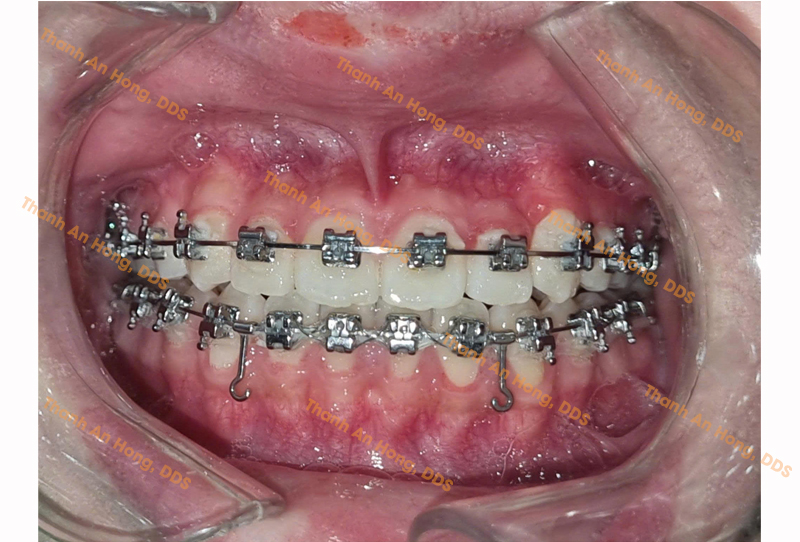

HÌNH ẢNH THỰC TẾ

Chỉnh mắc cài giảm hô